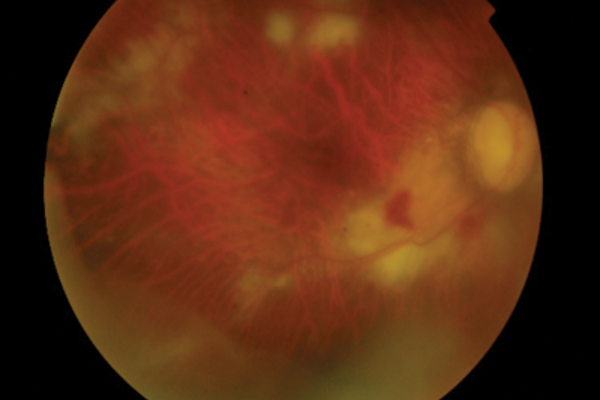

Cytomegalovirus retinitis post intravitreal triamcinolone in an immunocompetent patient with juvenile glaucoma